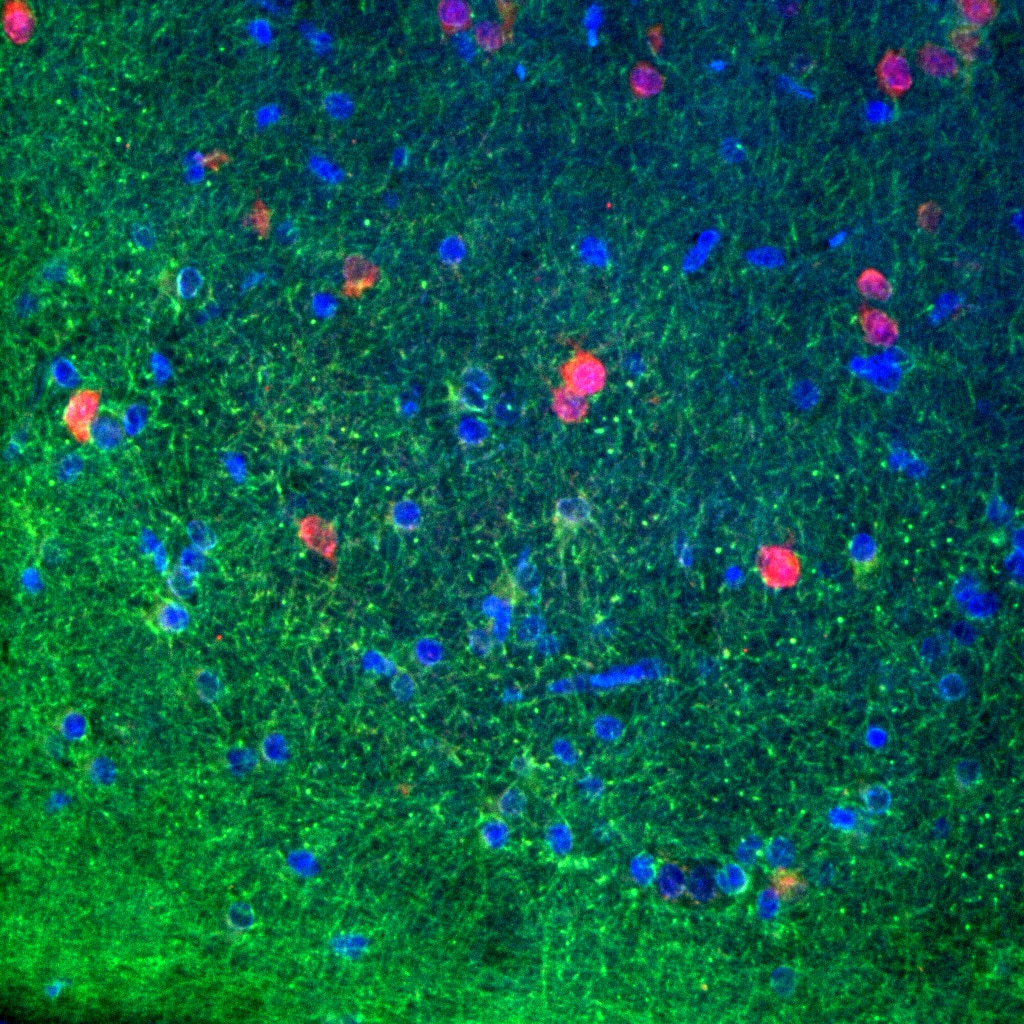

FH Reyes (Verified Customer) (09-24-2025) | NTRK3 or TRKC (in green) marked mainly a specific subtype of astrogliosis in FCD human tissue